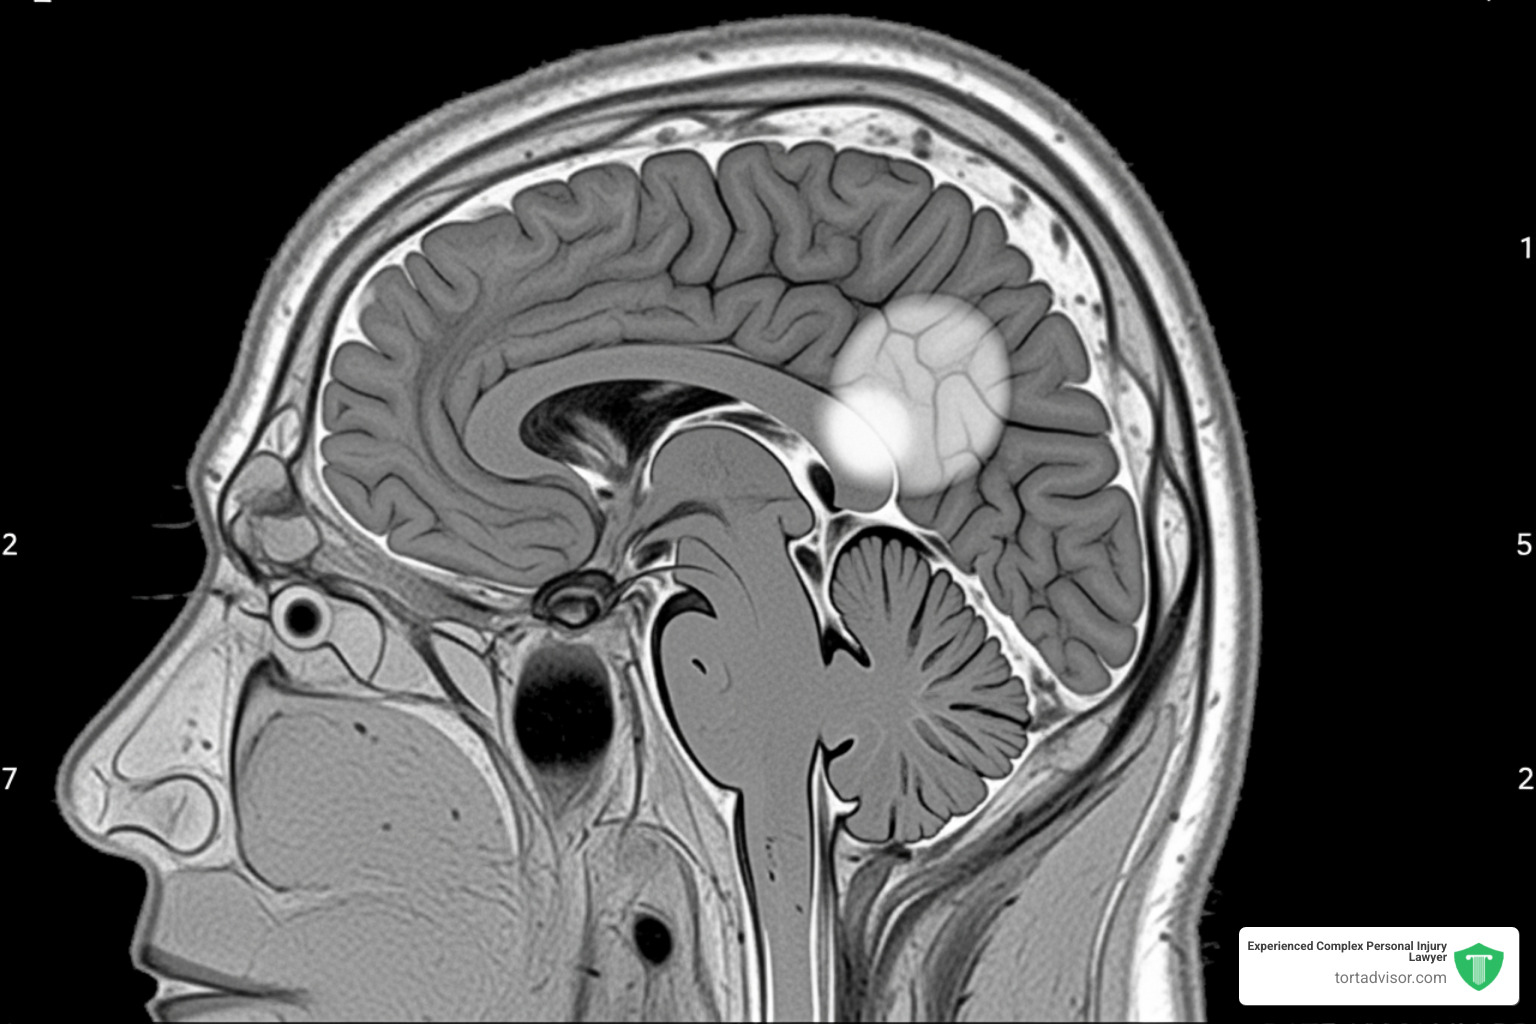

Meningiomas are tumors that grow on the protective tissues surrounding the brain and spinal cord. Though usually noncancerous, their growth inside the skull can press on brain tissue, causing serious symptoms.

A groundbreaking March 2024 study in The BMJ found that women who used Depo-Provera for over a year had a 5.6-fold increased risk of developing meningiomas. The study also showed that the longer the drug was used, the higher the risk became.

The biological link is plausible because meningiomas have progesterone receptors. The synthetic progestin in Depo-Provera may fuel the growth of these tumors. You can read the full March 2024 study in The BMJ for detailed findings.

This situation is especially troubling because while Depo-Provera labels in Canada, the UK, and Europe were updated to warn of meningioma risks, U.S. labels have not consistently included this warning. This discrepancy suggests American women were not given the same opportunity for informed consent. The FDA’s own data shows tumors (neoplasms) are the most reported side effect for Depo-Provera as of August 2024.